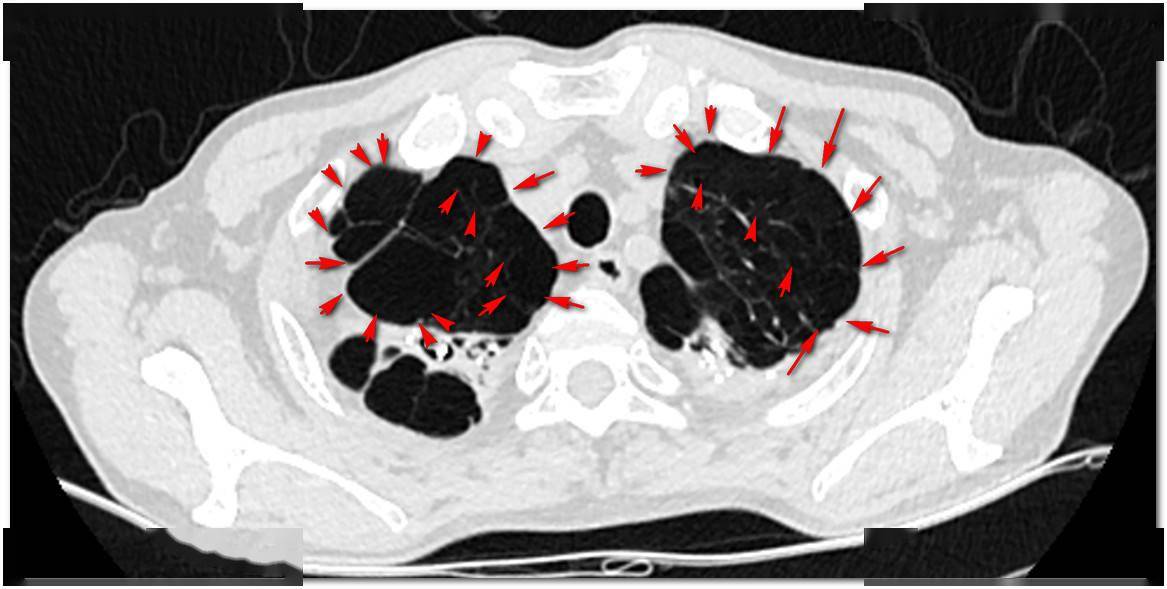

弥漫性肺泡出血

【影像读片】右肺毁损